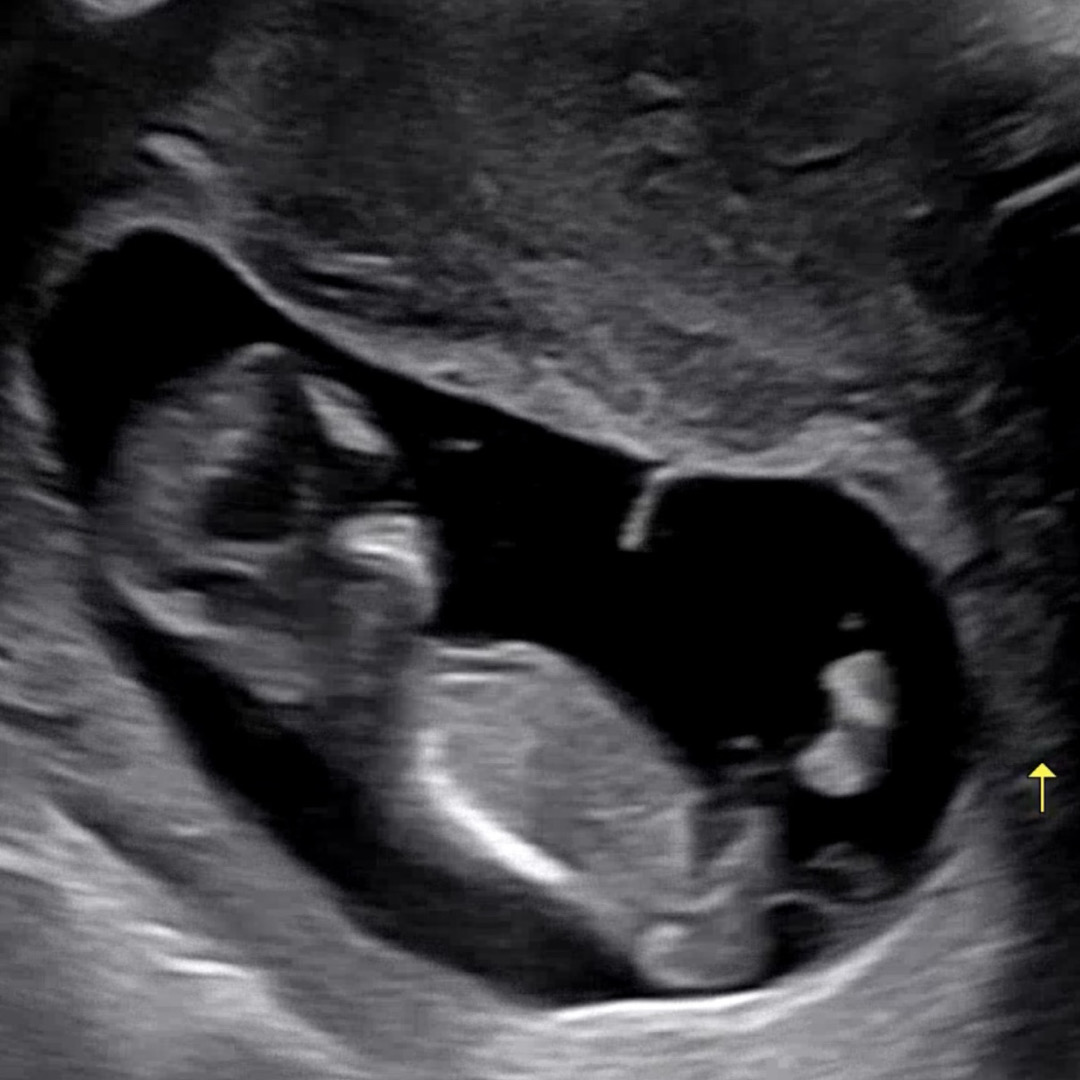

각도법 궁금해요🥹

제 눈에는 생식기가 안 보이는 것 같긴 한데,,,, 혹시 고수님들 눈에는 보이실까요🥲 각도법 엄청 연습했는데ㅋㅋㅋㅋㅋㅋㅋ 막상 제 아기 생식기는 알아보지도 못하겠네요🤣🤣

아들로 보여용🌶

아들 같아유...!